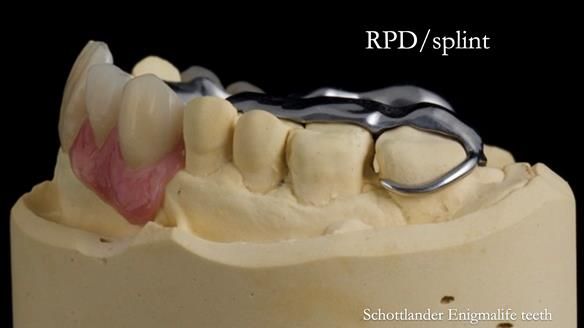

Welcome to Newsletter 67, where I will detail the making and fitting of an upper metal-based partial denture/splint (“Combat denture”) for Brian, a patient with a powerful locked occlusion and deep overbite. The full protocol workflow is presented here.

- Bruxism: The upper and lower teeth are worn and chipped due to heavy clenching and grinding. With a powerful bite and limited space for replacement teeth, dental implants supported fixed teeth are not recommended. A simpler solution is a metal-based partial denture/splint (“Combat denture”) as planned below. This will act as a splint to protect and replace the missing teeth.

Treatment Process: I provided the clinical work, while Rowan Garstang handled the technical work. The treatment required five visits to fit the RPD. The worn lower anterior teeth were then built up. Unfortunately, I did not check the guidance on the denture teeth after this, and tooth 11 fractured off the denture. Brian was very understanding, and I adjusted the denture thoroughly. It has been fracture-resistant and trouble-free for the last three years.